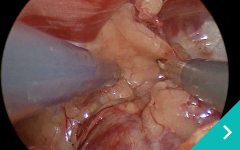

腹腔鏡手術は、この開腹手術の課題である患者さんの負担を軽減させるため、小さな傷口3つほどをあけ、胃や腸がある腹腔にCO2ガスを注入して膨らませてから内視鏡カメラやメスなどを挿入して手術する方法です。

ミニマム創内視鏡下手術は腹腔鏡だけでは対処ができないような手術の際に、お腹にラッププロテクターという器具を設置して行う腹腔鏡と開腹手術を組み合わせた手術です。